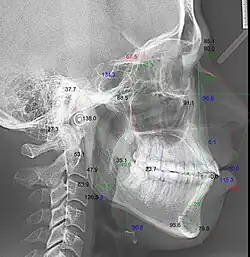

Кефалограмма — геометрическая обрисовка телерентгенограммы для изучения абстрактных закономерностей — угловых и линейных кефалометрических параметров[3][4].